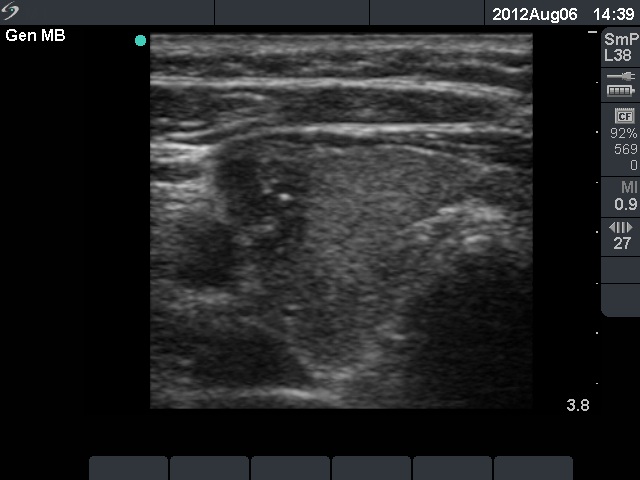

Papillary carcinoma (histological diagnosis) - case 684 |

This investigation was performed with an older equipment with worse resolution, therefore the granules are not only larger but a bit blurred compared with punctate echogenic foci presented in the former cases. |